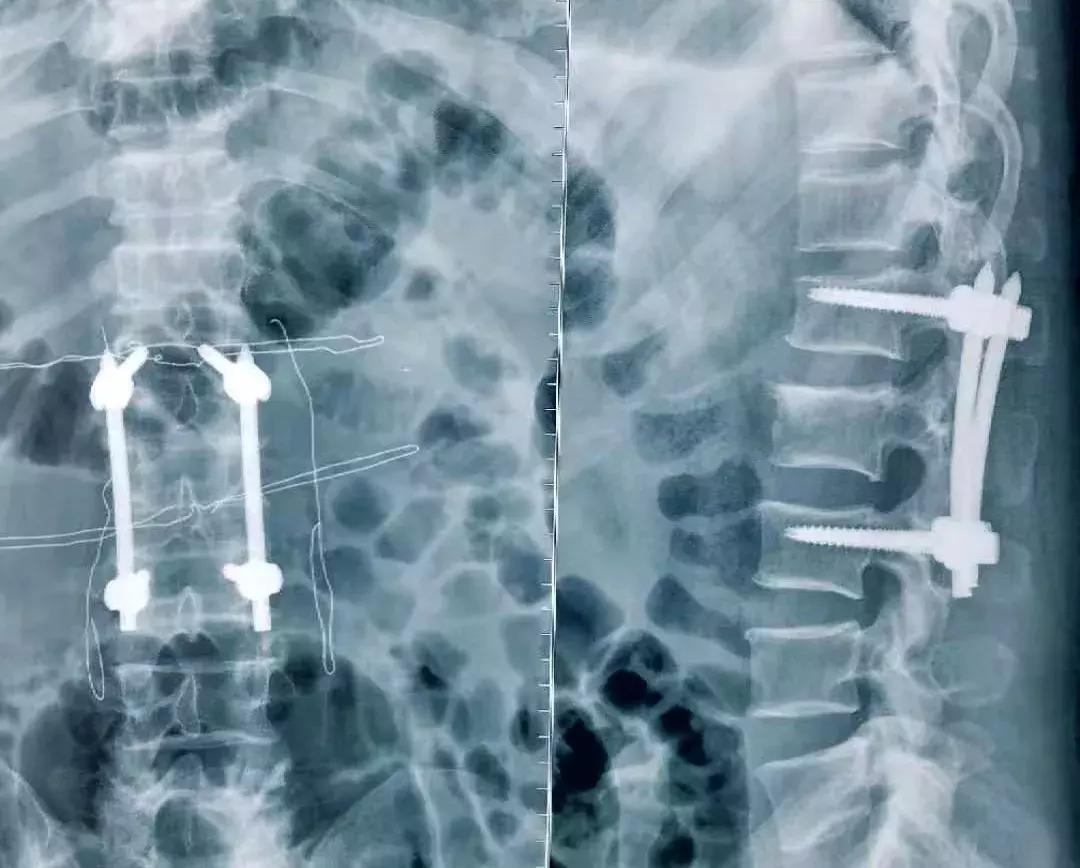

术后正侧位压缩椎体高度恢复,螺钉位置精确